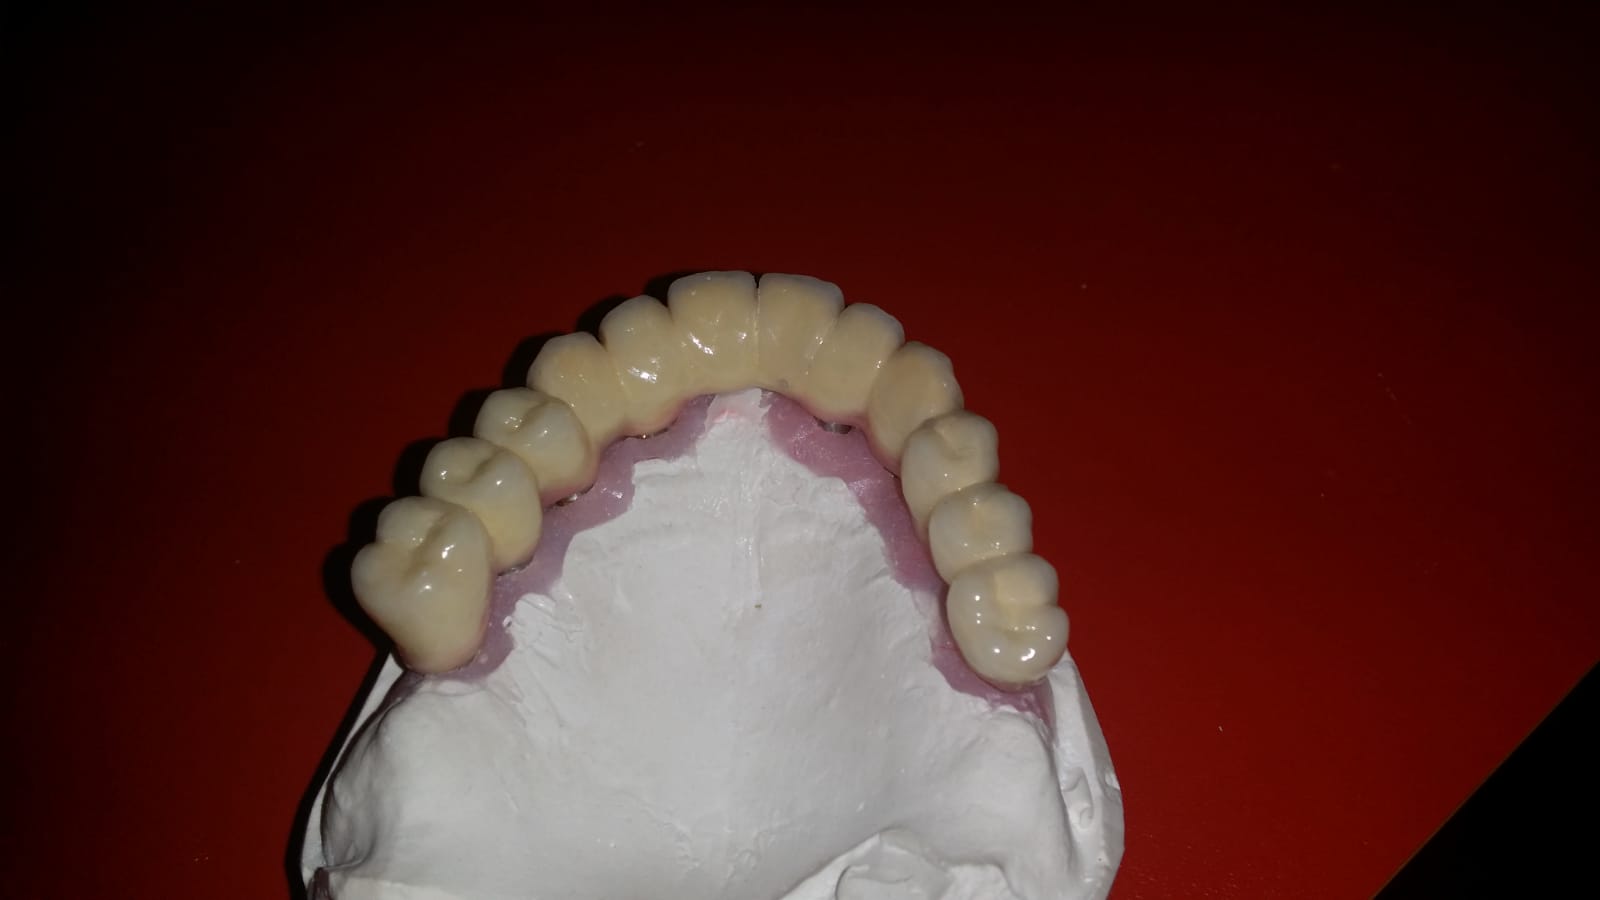

Punte realizată pe 4 implanturi dentare la mandibula și 6 implanturi la maxilar All in One

Punte fixa provizorie realizată la mandibula în 24 ore, pe 4 implanturi dentare

Punți metaloceramice total fizionomice pe implanturi

Punti totale pe implanturi